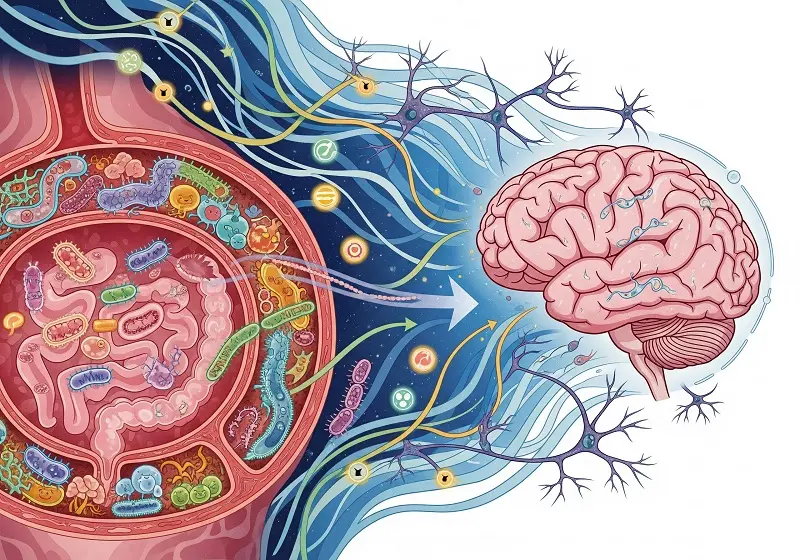

La Microbiota Intestinal y el Cerebro | Imagen superior de Google AI Studio

Durante años, la idea de que «somos lo que comemos» ha tenido un matiz metafórico. Sin embargo, la ciencia moderna nos muestra que esta afirmación es sorprendentemente literal. Especialmente en lo que respecta a la influencia del intestino en el cerebro. El eje intestino-cerebro es un sistema de comunicación bidireccional complejo que involucra vías nerviosas (como el nervio vago), endocrinas (hormonas) e inmunitarias. La microbiota intestinal, al producir una vasta gama de metabolitos, neurotransmisores (como serotonina, GABA) y moduladores inmunes, actúa como un potente regulador de esta comunicación.

El equipo del CSIC analizó perfiles de microbiota intestinal y los correlacionó con imágenes cerebrales de resonancia magnética en un grupo de participantes. Los hallazgos revelaron que ciertos patrones en la diversidad y composición de las bacterias intestinales estaban asociados con diferencias en el grosor cortical y la conectividad en regiones cerebrales clave.

Esto sugiere que la microbiota no solo influye en la función cerebral a nivel químico (neurotransmisores), sino que también podría tener un impacto en la propia anatomía funcional del cerebro. Así, moldea su estructura de una manera que afecta directamente cómo pensamos, sentimos y recordamos.